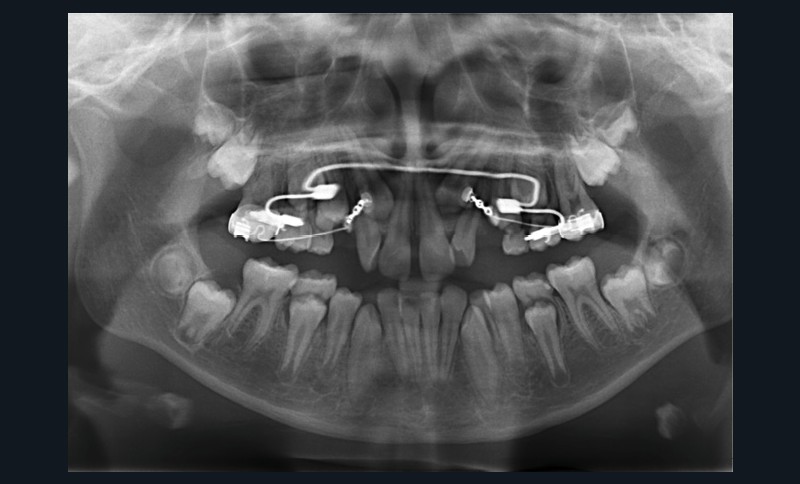

Une fois que la partie en alliage à mémoire de forme de l’arc transpalatin a retrouvé sa forme initiale, l’arc est désinséré. Les U latéraux et les lames d’insertions en acier sont réglés dans les trois sens de l’espace à l’aide d’une pince 139 pour corriger l’inclinaison mésio-distale, le torque et augmenter la dérotation de 16 et 26 pour assurer une traction supplémentaire des canines incluses en direction vestibulaire. Les bras d’expansion des secteurs latéraux de l’arc transpalatin sont également sectionnés. Les bras vestibulaires en TMA sont activés dans le sens vertical pour une traction des canines vers le plan occlusal.

Un appareil multi-attache est mis en place avec une prescription MBT en .022 x .028. une fois les faces vestibulaires des canines maxillaires apparentes. 13 et 23 ne sont pas prises en charge dans l’arc pour éviter les effets parasites sur les dents adjacentes. Leur traction est poursuivie avec des élastiques de Classe II (1/4” – 3.5 oz) en port nocturne. Ces élastiques sont portés sur un bouton palatin pour la 23 afin de corriger sa rotation mésio-vestibulaire. Une fois les canines suffisamment proches du plan occlusal, elles sont prises en charge dans un arc continu en suivant les séquences suivantes : .014, .018 et .019 x .025 Niti. Une fois l’arc .019 x .025 en Niti en place pendant huit semaines, l’arc transpalatin est déposé. L’arcade mandibulaire suit cette même séquence d’arcs avec l’ajout d’un arc en acier .019 x .025 avec courbe de Spee inversée pour aider à la correction de la supraclusion.

À ce stade, une radiographie panoramique est réalisée pour s’assurer de l’intégrité des racines, contrôler les axes dentaires et planifier le repositionnement de certaines attaches ainsi que le collage des tubes sur les secondes molaires en cours d’éruption.